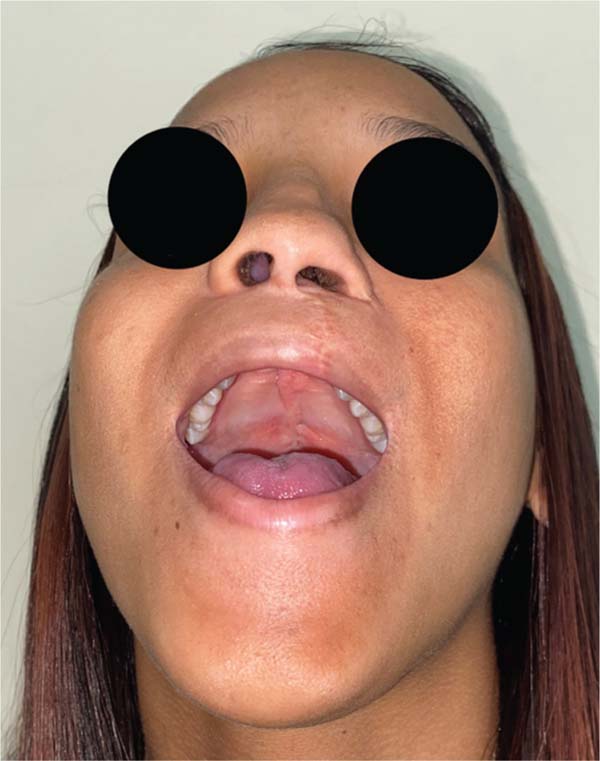

Uma análise adicional revelou que um dos pacientes apresentava um distúrbio comportamental com movimentos repetitivos mão-boca, conforme relatado pela mãe. No segundo caso, foi observada uma fossa velopalatina nas fotos pré-operatórias, e uma dissecção inadequada contribuiu para a formação da fístula pelo cirurgião (►Figs. 4–11).

Os casos de fístula na Zona II foram analisados, e identi-ficou-se um distúrbio comportamental em um dos casos, com diagnóstico de autismo leve e relatos maternos de movimentos repetitivos mão-boca. No segundo caso, uma fossa velopalatina foi notada nas fotos pré-operatórias, o que indicava dissecção inadequada como causa da fístula. É crucial analisar individualmente os casos de FON para entender os fatores contribuintes e aprimorar a abordagem cirúrgica para reduzir sua incidência.